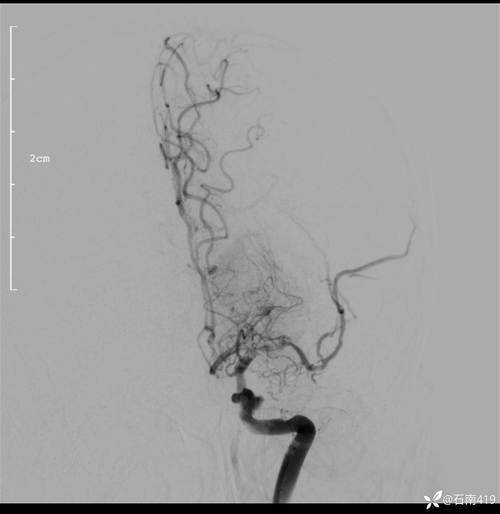

| DSA (数字减影血管造影) | “金标准”,空间分辨率最高,能动态显示血流;可同时进行血管内治疗(如取栓、支架植入)。 | 有创性检查,属于小型手术;有穿刺点出血、血管损伤、 stroke 等风险;检查费用高。 | 当CTA/MRA结果不明确时;或计划进行血管内介入治疗时。 |

对于脑梗患者来说,CTA是一项至关重要的检查,它像一张“作战地图”,能快速、准确地告诉医生“敌情”(血管堵塞情况在哪里、多严重),从而决定最佳的“作战方案”(是溶栓、取栓还是药物治疗),并预测“战后结果”(预后)。